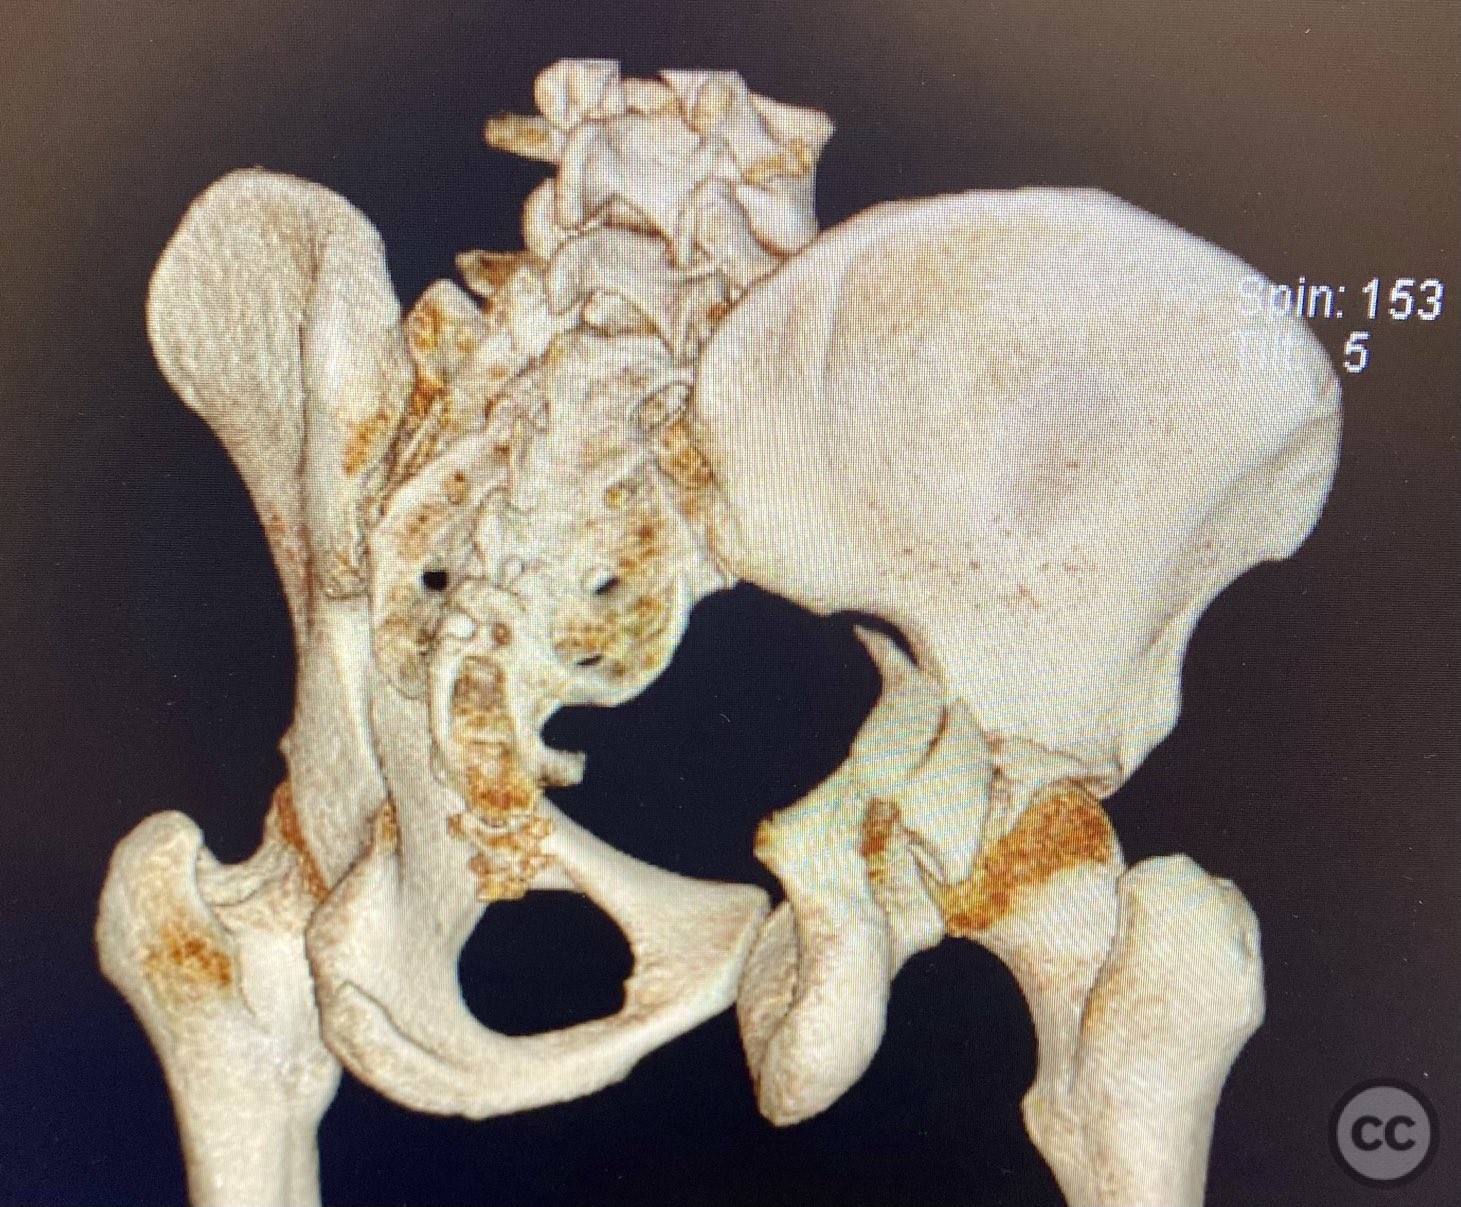

Posterior Wall Acetabular Fracture-Dislo...

Texas, United States

Pelvis - AO/OTA 6x

Complex Acetabular Posterior Wall and Tr...

Posterior Medial Dome Impaction in Assoc...

Posterior Wall and Transverse Acetabular...

Posterior Wall Acetabular Fracture with...

Transverse with Comminuted Posterior Wal...

Unstable Displaced Posterior Column/Post...